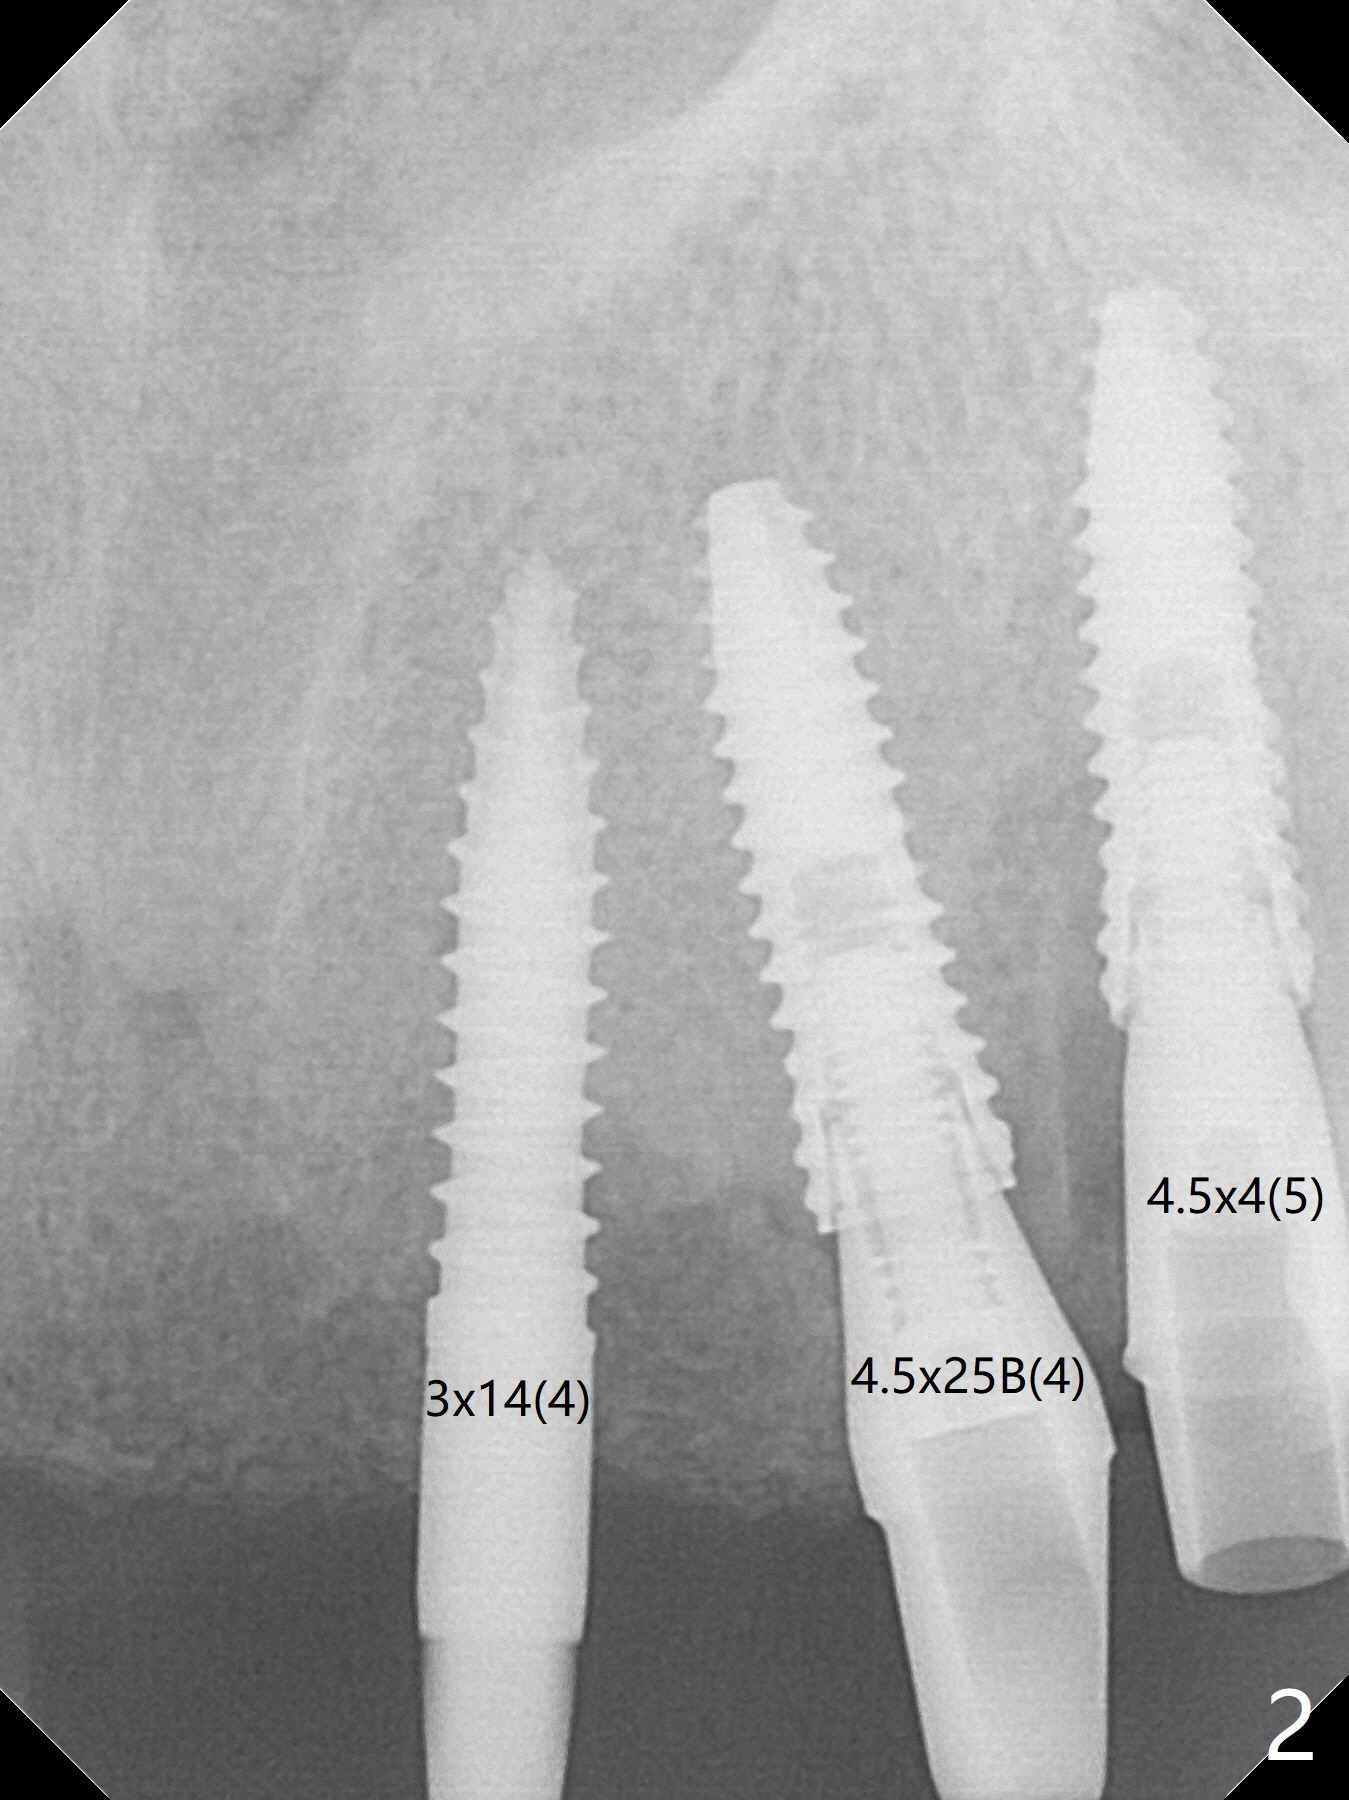

It is smooth and quick to finish osteotomy with guide at #6,7,10-12, but when 3 mm 1-piece implants are placed free hand at #7 and 10 (Fig.1,2), the gingival parts of the abutments contact the incisal edges of the lower incisors (anterior deep bite) in spite of effort to change the trajectory by repeated back and forth placement after use of Lindamann bur buccally. Following an immediate provisional (Fig.3,4), the occlusal surface of the posterior teeth are raised to eliminate anterior restoration interference. Immediate postop CBCT shows that the implants at #7 and 10 could be placed more buccally (Fig.6,7, as compared to the normal position at #6,11,12 (Fig.5,8,9)). Fig.10 was taken 2 days preop, while Fig.11-13 postop. Can we change 1-piece implants (3mm) at #7 and 10 to 2-piece one (3.5) and use angled or cementation abutments for easy restoration (Fig.14-16)?